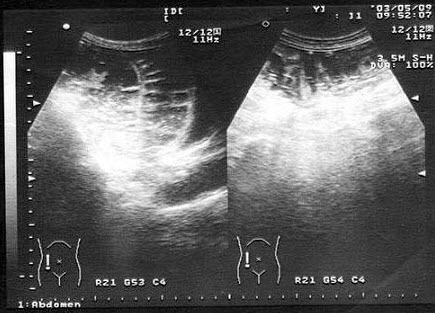

女性,于膀胱输尿管位置见一囊性光团,有规律收缩,增大。如图所示,考虑为()

A.膀胱肿瘤

B.膀胱憩室

C.输尿管结石

D.输尿管囊肿

E.膀胱异物